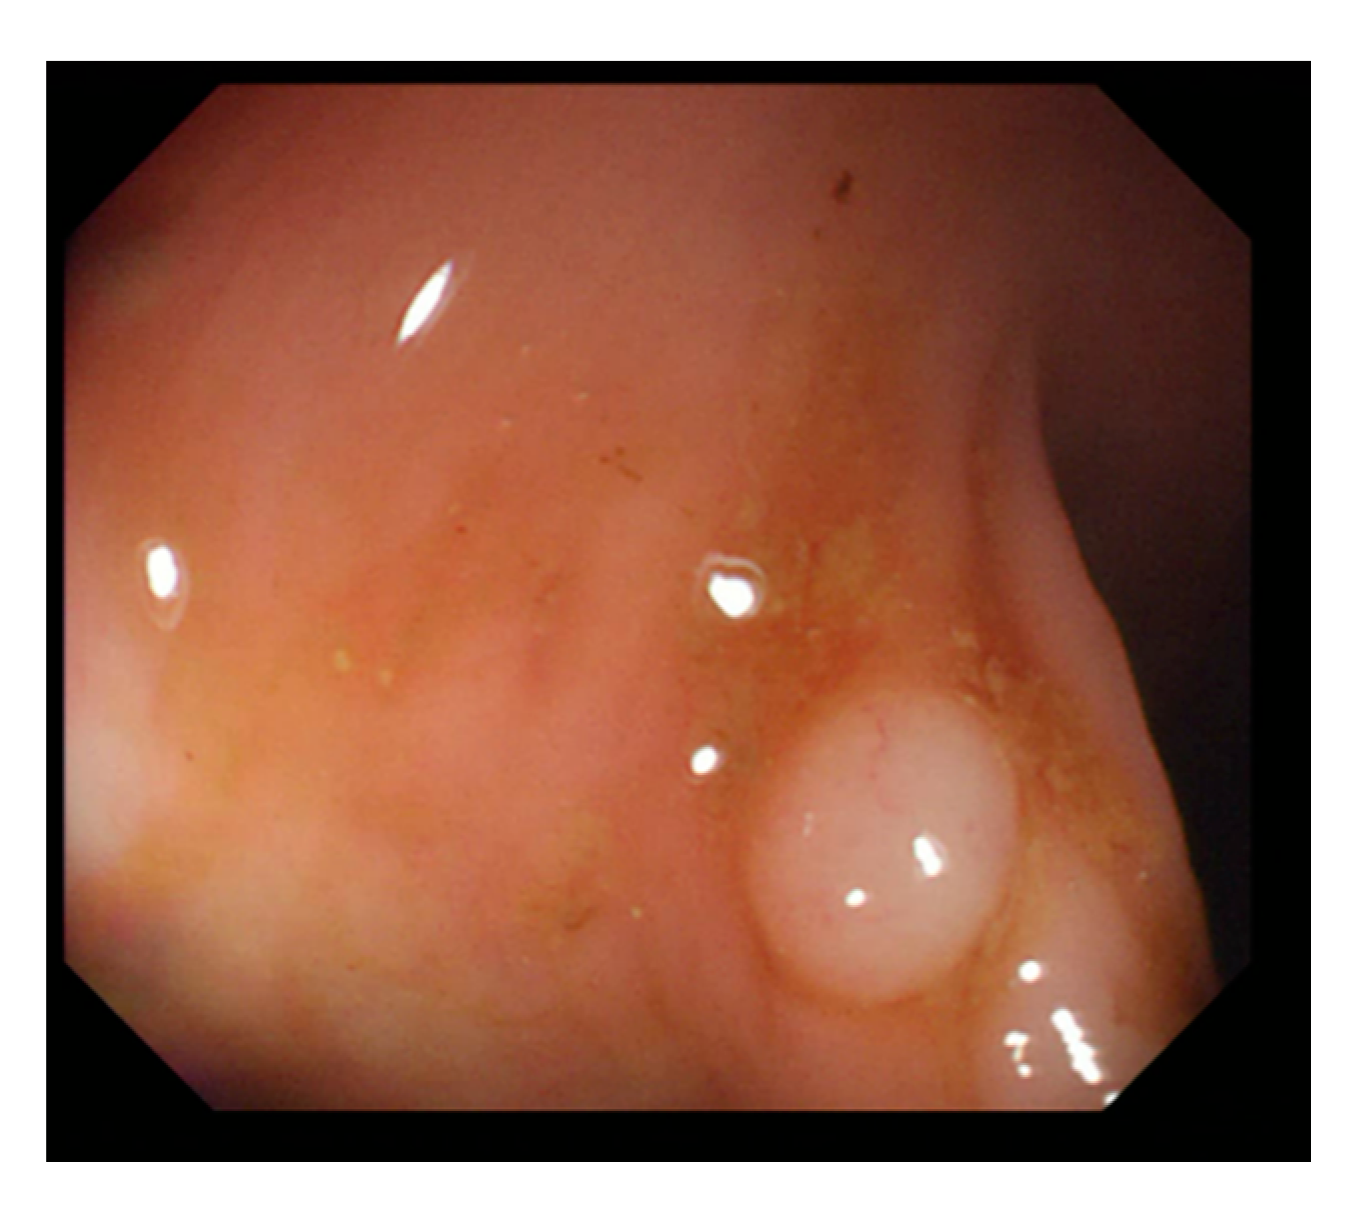

Currently, many medical images are processed into grayscale images, such as ultrasound, computed tomography (CT), and magnetic resonance (MR) images. Tan et al. [44] applied a gray-level cooccurrence matrix and CNN to CT images for polyp diagnosis. Zhang et al. [45] compress the three-channel color images of chest CT to grayscale images. A five-layer deep CNN with stochastic pooling is used to diagnose chest-based COVID-19. Xie et al. [46] mentioned that in deep learning, colors are not the key features influencing accurate image classification. They also discovered that in X-ray image classification, the speed and accuracy of processing grayscale images were considerably higher than those of processing RGB images. The grayscale method used was ITU-R Recommendation BT.601 [47]. Moreover, misjudgments were easily made in the presence of excessive intestinal wall textures, when polyps were too small (Figure 2), and when polyp textures were similar (Figure 3) to intestinal wall textures.

Figure 3.

Small texture of polyp and intestinal wall.